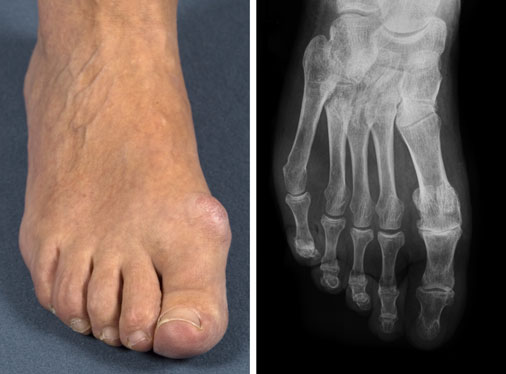

Patientin mit Großzehengrundgelenksarthrose vor der OP klinisch und im Röntgenbild

Die schmerzhaft eingeschränkte Beweglichkeit des MTP 1-Gelenks in Dorsalextension sowohl im belasteten als auch unbelasteten Zustand sind die Hauptbeschwerden des Hallux rigidus-Patienten. Oft können die dorsalen Osteophyten als „dorsaler Kranz“ palpiert werden und bereiten zusätzliche Beschwerden beim Tragen von Schuhwerk. Druckschmerz am Metatarsale-Köpfchen 1 ist auslösbar.